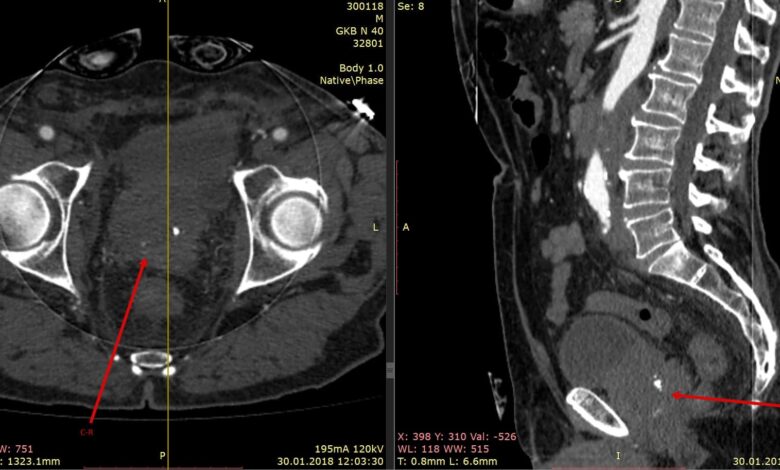

Сама процедура КТ брюшной полости с контрастным веществом представляет собой сканирование органов брюшной полости с использованием специального аппарата. Пациент ложится на стол, который скользит внутрь тоннеля сканера. Во время сканирования важно лежать неподвижно, чтобы изображения получились четкими и точными.

Во время процедуры пациенту могут ввести контрастное вещество через вену для более детального изучения органов. Контрастное вещество помогает выделить сосуды, опухоли или другие изменения в тканях, делая результаты более информативными.